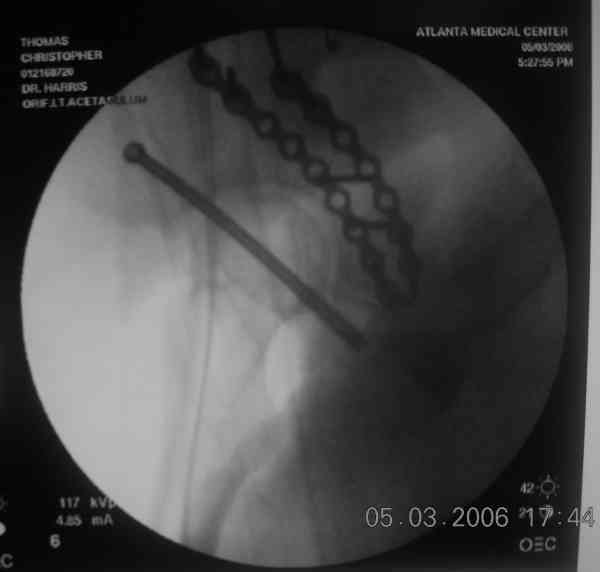

The 2nd example is of a motorcyclist with a transverse fracture-dislocation...he had a closed attempted reduction and placed in traction but the manipulative reduction was not concentric (not unusual for this injury pattern)...so the traction was adjusted to be just enough to disengage the head from the fracture (12#) until he could be cleared for surgery one day after injury...he was treated "urgently" then with a prone KL, clean the fracture, reduce and clamp it, screw it, support with a balanced plate, close, and enjoy...2-3hours, 400cc EBL, blah, blah, blah..

Prone

Here's a pic from the foot of the bed and you can see the clamp in the wound and the knee is extended so he must've had a tight rectus. The C-arm is rolled back to an obturator oblique image to reveal the anterior column...we put a slight outlet tilt to combine the images and give a better view of the anterior column...we can see the posterior column limb reduction in the wound, we can palpate the quadrilateral surface limb, and the image demonstrates the anterior column portion...you can adjust the tilt and rotation to image tangentially to the fracture plane if you'd like. We've inserted a 2mm K wire to site the starting point and aim/orientation for the drill and screw

Prone Imaging

same image, just another look.

Prone Inlet

OK, now we're inserting the drill percutaneosuy using a sleeve. This fluoro shot is not for this patient (notice no clamp) but I was too lazy to go searching the PACS for one with the clamp on, so pretend...I'll save the next ones and send along...the imaging is the same and the clamp doesn't obstruct imaging other than very rarely...you can always tilt the C-arm a bit to clear it if the clamp obstructs the exact spot that you'd like to see. We'll assume that everyone knows the safe zone for a medullary ramus screw. Use a calibrated drill and sleeve of known length to simplify your life...or use Alex's fancy cannulated screws...I like 3.5mm screws because the oscillating 2.5mm drill bounces and remains intraosseus when it oscillates and contacts endosteal cortical ramus... so will the screw, and like a long bent screw IF the fracture is clamped... if unclamped, when the screw contacts the endosteum, it pushes the reduction apart instead of bouncing. The big 7mm cannulated screws fit few patients and extrude...we very rarely use them any more...you'll see an old one later.

Prone Obturator-Outlet

Screw insertion using the obturator-outlet combination image.

12.Prone Obturator-Outlet

Same with a contoured pelvic reconstruction plate applied and tensioned.

Prone Iliac Oblique

The other oblique reveals the extra-articular implants.... you know the AC screw is extra-articular from the other views.

Routine Fixation

AC Screw

PC Neutr Plate

Others

The unstable caudal segment is secured by the lower 2 plate screws and the AC medullary screw... always assure that your fixation is sufficient to defeat the instability... part of your prop plan... but assure it before you close... it¹s your last chance... you shouldn't have to be pushing on the hip in contorted ways to determine your fixation stability...you can if that makes you 'comfortable'.